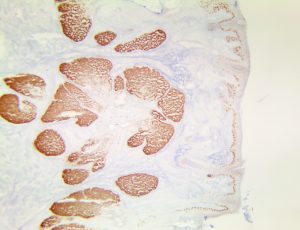

Bio SB has developed high affinity IVD monoclonal antibodies for fast immunohistochemistry (IHC) detection of melanoma, basal cell carcinoma (BCC), squamous cell carcinoma (SCC) and other Mohs surgery related conditions. Combined with our innovative IHC detection systems, we are opening the doors to a faster and more accurate immunohistochemistry applicable to Mohs surgery.

Bio SB has developed a fast, non-biotin monovalent Fab micropolymer IHC detection system for the detection of IVD antibodies for melanoma, BCC, SCC and other Mohs surgery related conditions. Our innovative IHC detection systems have opened the doors for a faster and accurate immunohistochemistry applicable to Mohs surgery.